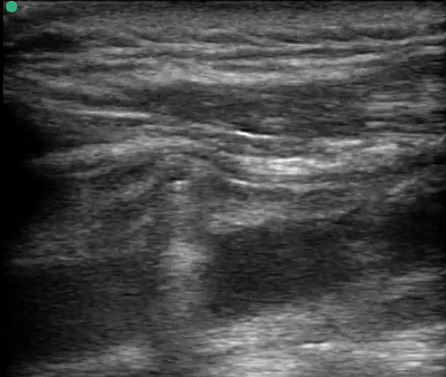

POC Ultrasound neck done in ED showed the bullet lying anterior to the IJV.